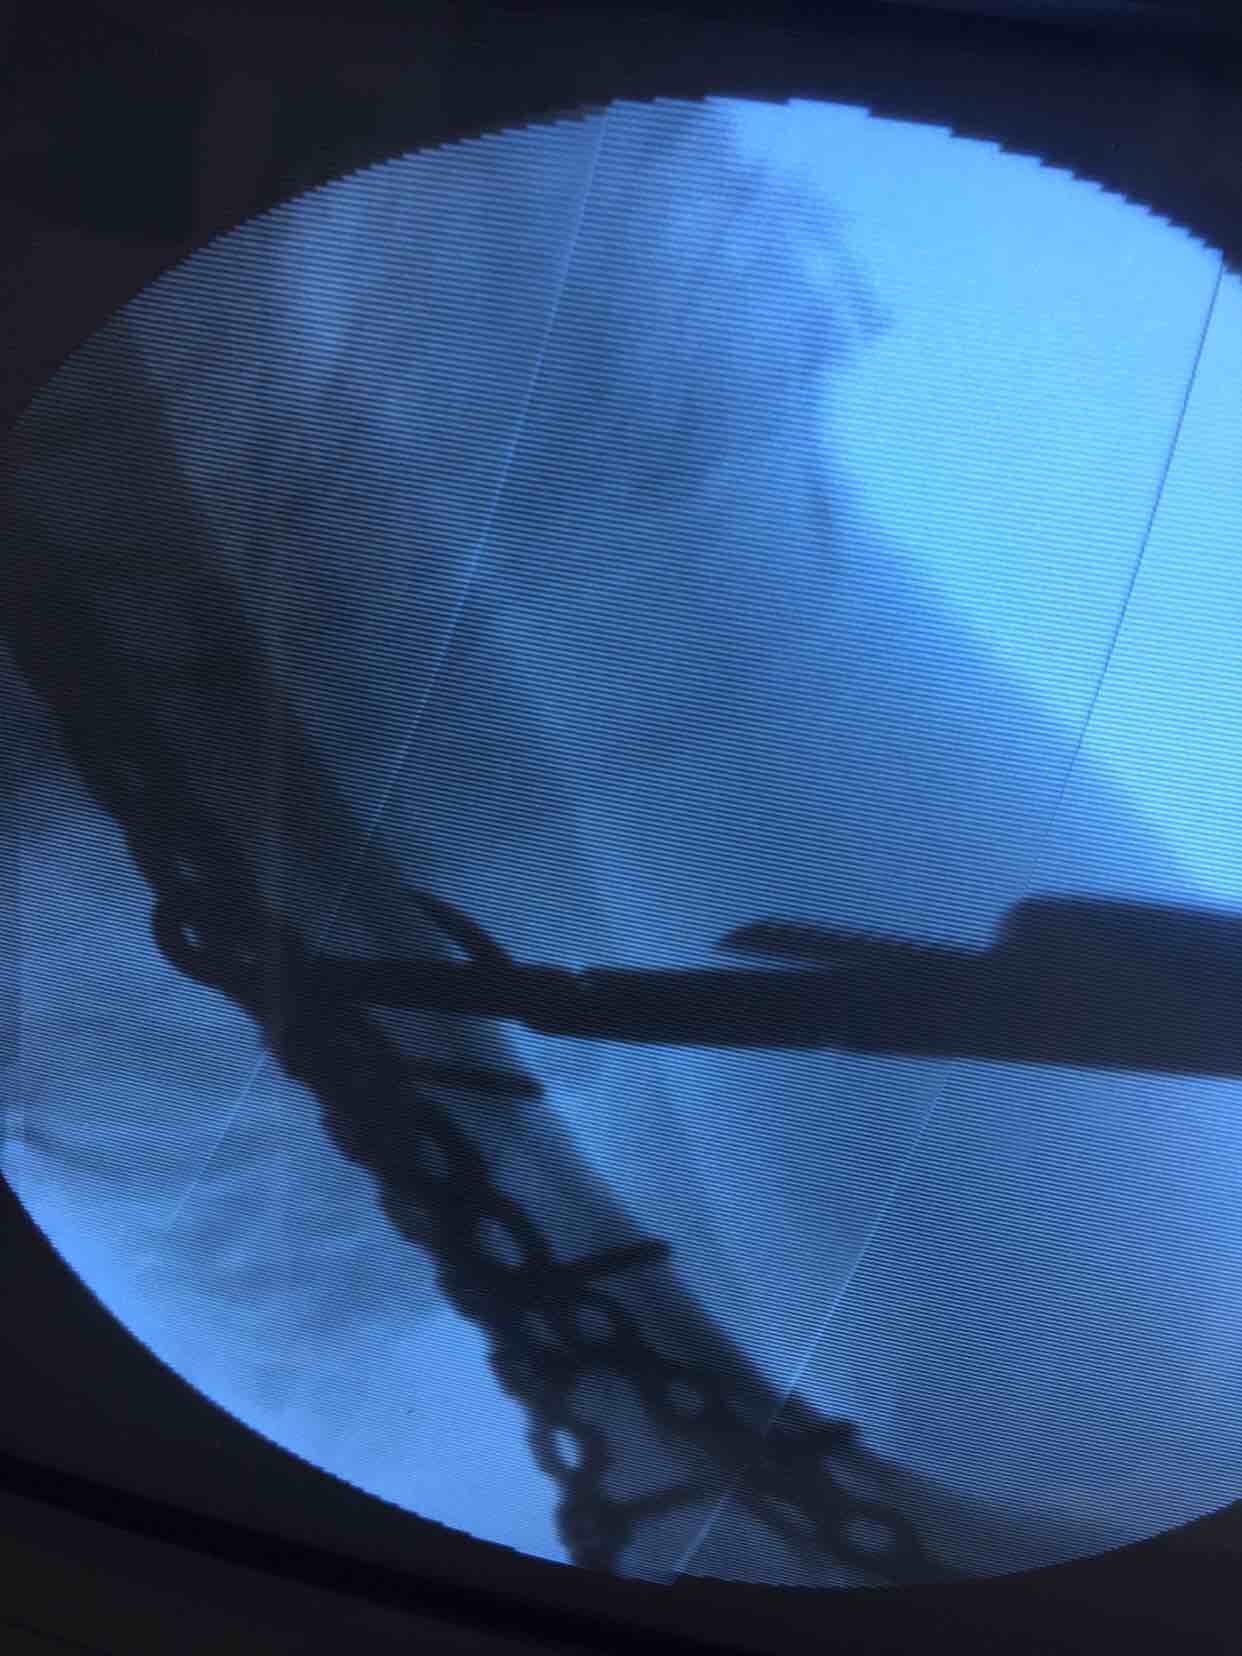

肱骨远端骨折(切复双钛板内固定)

诊断肱骨远端骨折在臂丛麻醉下行切复内固定术,术后抗炎,消肿等处理。